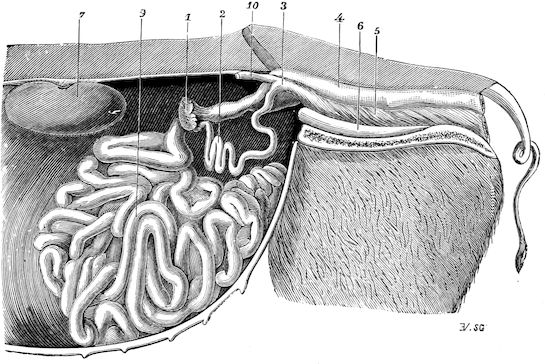

Fig. 8.—Transverse section through the middle region of the face in a pig suffering from osseous cachexia.

18In the final stages, the bones may be cut with a knife, and a time arrives when bony tissue seems completely to have disappeared; thus, as shown in Fig. 8 herewith, it was possible to cut the entire head of a pig into thin slices without the slightest difficulty. All parts of the head had been affected by the softening change.

From the chemical point of view, the diminution in mineral salts and in phosphate of calcium has long been recognised, but the degree of this change varies according to the phase. In human beings the proportions have been estimated as follows: Normal bone, 50 to 80 per cent. of phosphate of calcium; bone in persons suffering from osteomalacia, 5 to 20 per cent. of phosphate of calcium. The changes in the ossein have not been carefully studied. We only know that histologically the ossein becomes fibrillar, and that chemically it no longer retains its normal composition.